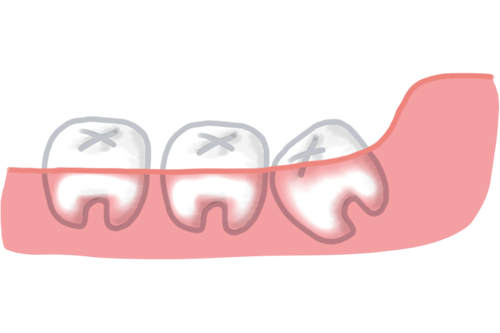

「自家歯牙移植(じかしがいしょく)」とは、ご自身の歯(主に親知らず)を別の場所に移植する治療です。奥歯など他の歯が抜けてしまった際に、温存していた親知らずを移植することで自分の歯で噛める状態を取り戻せる可能性があります。

インプラントや入れ歯が「人工物で補う」治療であるのに対し、自家歯牙移植は自分の歯を使うため、自然な感触に近い噛み心地が期待できます。また、条件が合えば保険診療の対象となる場合があります。ただし保険適用には「保存不可能な歯を抜歯するのと同時に、その場所へ親知らずを移植すること(抜歯即時移植)」という条件が必要で、すでに歯が抜けている場所への移植は自由診療となるケースも多いです。

保存不可能になった奥歯の位置に親知らずを移植する自家歯牙移植の流れを示した図

親知らず(第三大臼歯)は、すべてが抜歯の対象になるわけではなく、条件によっては保存し将来的に活用できる場合があります。特に、自家歯牙移植に利用できるケースでは、あえて抜かないで残しておくことが検討されます。